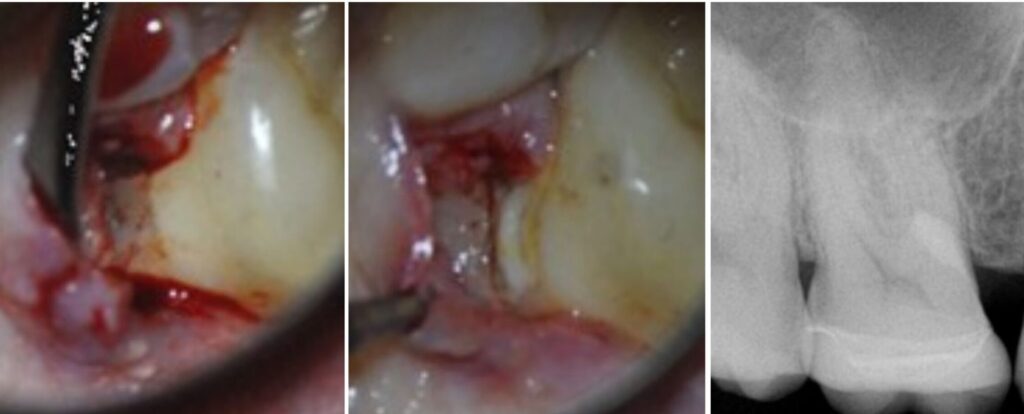

• Cervical resorption? Now that’s a game of strategy. You might be doin’ a surgical flap, trichloroacetic acid, curettage, restoration, prayer

Surigical cervical resoprtion MP UR6. NB repair only, RCT not required